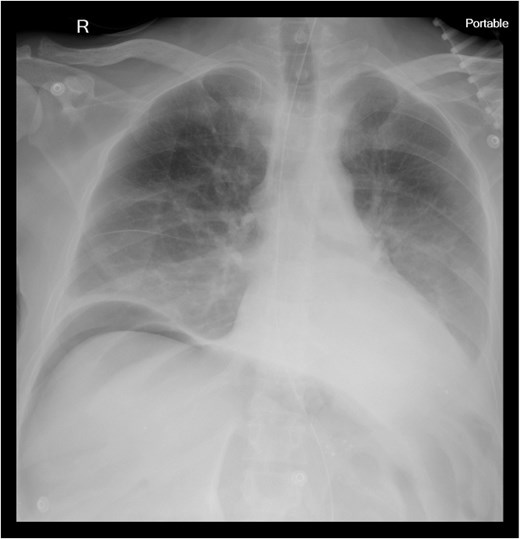

Chest X-ray revealed pneumoperitoneum (Fig. 1), and computed tomography (CT) scan confirmed free intraperitoneal air with no evident abscess (Fig. 2). The patient was admitted to the intensive care unit, resuscitated, and underwent urgent exploratory laparotomy.